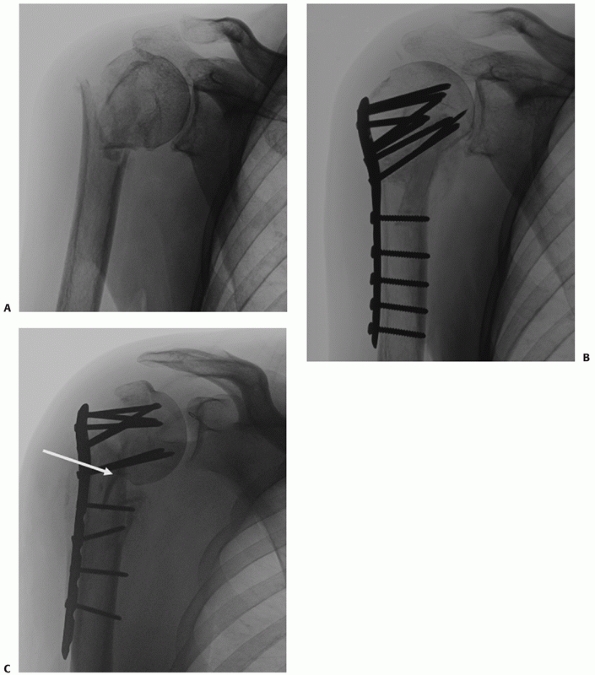

![]() |

|

FIGURE 35-14

Three- and four-part impacted valgus fractures show considerable variation radiologically and on three-dimensional computed tomography reconstructions (as shown), ranging from fractures that are minimally displaced (A), through more severe valgus angulation (B) to displacement with lateral translation of the head, where the medial soft tissue hinge is disrupted (arrow) and the risk of osteonecrosis is higher (C,D). |